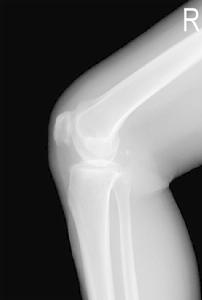

常規X線平片檢查時,可以發現掌指關節和近側指間關節的關節下有囊腫形成、骨侵蝕、關節間隙狹窄和骨贅形成,在腕骨和下尺橈關節亦有囊腫形成和侵蝕,少數遠側指間關節也可有變化。關節下囊腫最早出現,通常位於關節近側,常見的是掌骨頭部的關節下區有直徑1~3mm的圓形或卵圓形的小囊腫,周邊有界限清晰的硬化區。隨後出現關節間隙狹窄和骨贅形成,關節間隙狹窄不均勻,在關節受侵蝕處最為明顯。但關節間隙狹窄並不一定與囊腫形成相一致,有時可有數個關節下囊腫形成而無關節間隙狹窄;也可以有明顯的關節間隙狹窄而無囊腫形成。骨贅形成一般是關節嚴重受累的表現,但並不一定伴有明顯的關節間隙狹窄,腕骨內可有邊界清晰的囊腫,其直徑5~6mm,常為多發性;同一骨內也可有2~3個囊腫,常見於頭狀骨、鉤骨、舟骨和月骨 部分患者的遠端尺橈關節和尺骨遠端也可能有改變。在尺骨遠端和莖突處可有數處囊腫和骨侵蝕。少數病例可在該關節的橈側出現囊腫,甚至在三角韌帶處顯示混濁陰影。

在膝、髖等較大關節的X線表現主要是軟骨混濁,此乃由於軟骨鈣化或鐵質沉積之故。